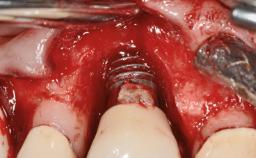

Removal of a Malpositioned Implant and Direct New Implant Placement with Simultaneous Contour Augmentation using GBR

A 35-year old female patient was referred to the Department of Oral Surgery and Stomatology at the University of Bern, Switzerland, for examination of an implant site that had exhibited clinical signs of slightly delayed wound healing. In addition, the referring clinician found no evidence for a facial bone wall when she raised a flap to gain access to the implant for abutment connection. Four months earlier, she had inserted a bone-level implant in a single-tooth gap, where the lateral incisor had been extracted due to a chronic periapical lesion on the mesial aspect of the root. Implant placement was combined with simultaneous bone augmentation using deproteinized bovine bone mineral (DBBM, Bio-Oss®; Geistlich, Wolhusen, Switzerland) and a collagen membrane (Bio- Gide®; Geistlich), followed by primary wound closure. The patient also provided the postsurgical radiograph that displayed the implant with a 3.5-mm healing cap.